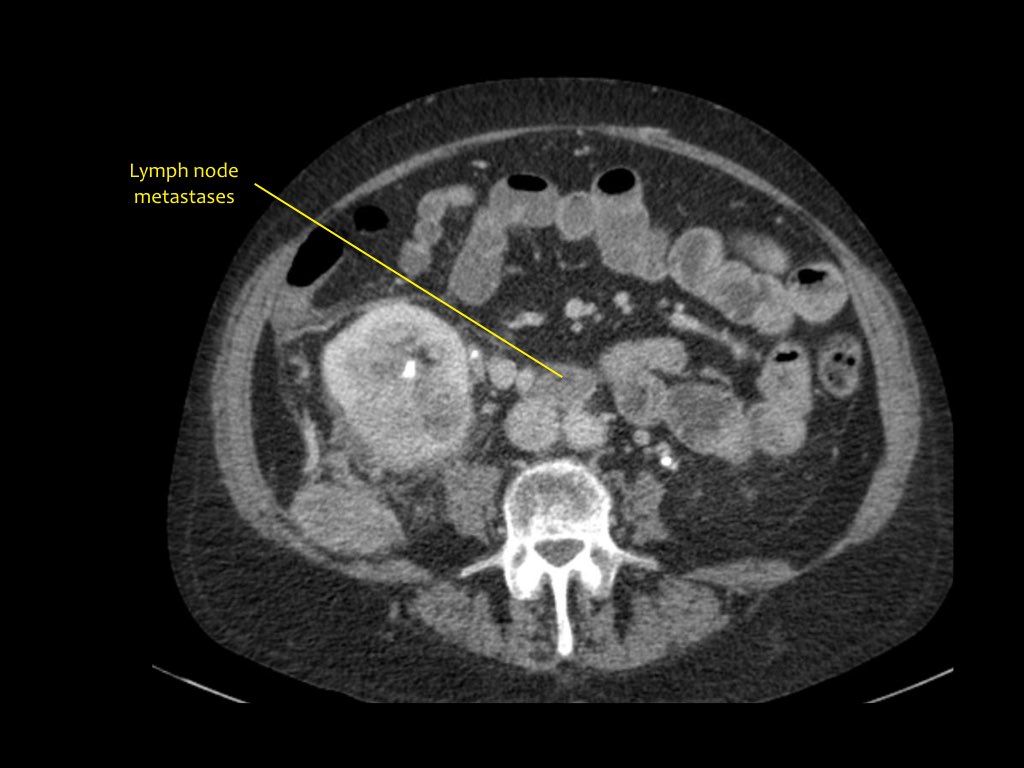

Tổn thương xâm lấn ở cực dưới thận phải, phát triển đáng kể sau sáu tháng, kèm theo hạch bạch huyết lan rộng. Đây được xác định là di căn của ung thư phổi.

Có một tổn thương di căn ở thận trái và nhiều tổn thương di căn hạch bạch huyết (mũi tên).

Nếu đây là biểu hiện duy nhất, sẽ rất khó để phân biệt với ung thư biểu mô tế bào thận có di căn hạch bạch huyết.